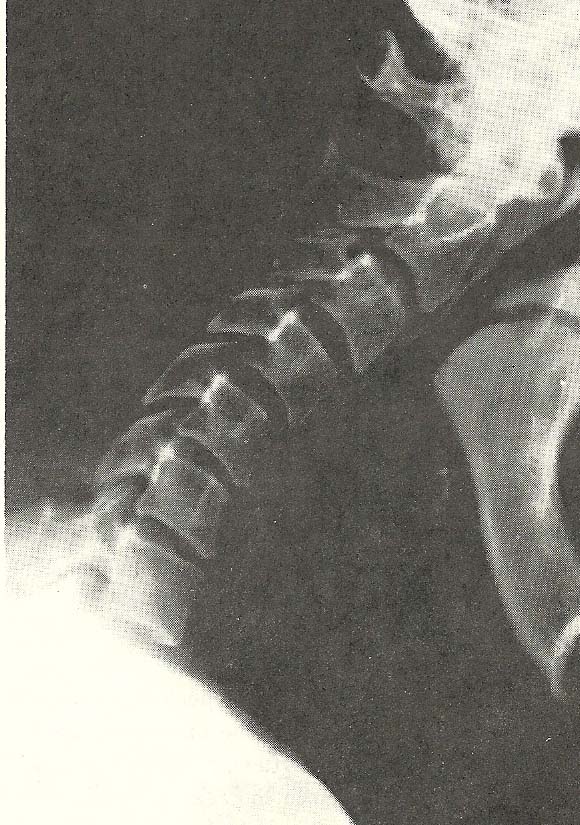

Case Illustrating Classifications C-4 and B-1

Another instance of altered vertebral mobility is shown in this case. The

altered cervical curve (hyperlordosis) shown in the neutral lateral film is

obviously associated with minor anomalies of the vertebral arches and

articular processes at C2--C4 (Fig. 6.79). There is also obvious arthrosis of

the facets throughout the neck, especially at C2-C3, and disc wedging to the

posterior is evident at C3-C4.

Flexion of the neck (Fig. 6.80) is grossly abnormal, the motion occurring

mainly as anterior bending of the neck as a unit --the lordosis remaining

essentially unchanged compared to the neutral film (Fig. 6.79). This

illustrates extreme hypomobility of nearly every cervical motion unit (B-1)

and abnormal motion of the cervical spine as a whole (C-4).

Extension of the neck is fairly well accomplished overall. At individual

motion units, however, one can see signs of restriction or hypomobility,

especially at C6 and C7 (B-1) where a comparison with the neutral film shows

little intervertebral extension (Fig. 6.81).

This 70-year-old male had a long history of neck pain and stiffness

associated with frequent headaches and bilateral shoulder pain. Orthopedic

tests showed diminished ranges of motion in all directions in the neck.

Cervical compression tests were negative.